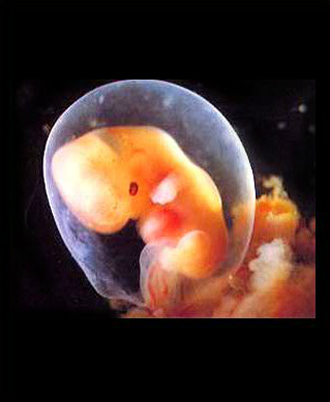

- 초기 정밀 초음파

- 복부 초음파